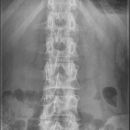

LWS a.p. stehend

Es wurden keine Bilder gefunden.

Kassette/Abstand

Format 20/40 hoch / FFA 1,15m

Lagerung

Patient steht mit dem Rücken am Rasterwandstativ, Arme längs des Körpers, evtl. Beckenschiefstand oder Beinverkürzung ausgleichen. Zur Darstellung der ISF darf das Format nicht eingeblendet werden! Keine Bleischürze - falls möglich Hodenkapsel/Schmetterling

Zentralstrahl

Senkrecht auf WS und oberen hinteren Beckenkamm.

Bemerkung

Schuhe ausziehen.

Qualitätskriterien

Scharfe und orthograde Abbildung aller Lendenwirbel mit ihren Querfortsätzen, der Kreuzdarmbeingelenke und des thorakolumbalen Überganges. Die Dornfortsätze sind mittelständig. Zwischenwirbelraum frei projiziert.